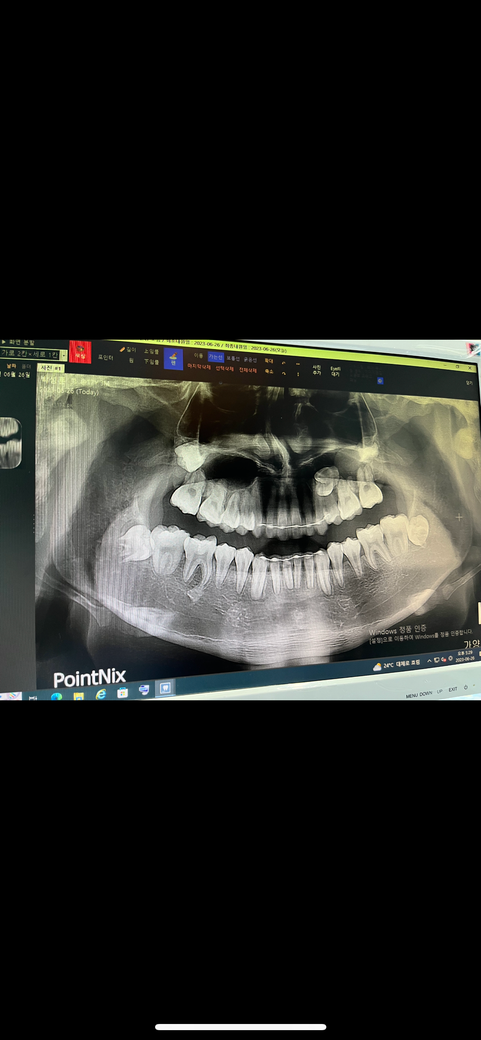

치아교정 끝나고 유지장치하는데 치아뿌리 많이 짧나여

그리고 사랑니 저거 뽑아야하나여 진짜 진지하게 대답해주세오 ㅜㅜ 이것때문에 잠도 못자요

1.뿌리가 많이 짧나요

2.저 사랑니들 다 뽑아야하나요

3.저 비발치로해서 매복이 저렇게 나둬도 되나요

-아래 앞니는 치아 뿌리가 다른분에 비해서 짧습니다.

-사랑니는 지금은 뽑지 않으셔도 될것같습니다.

3.저 비발치로해서 매복이 저렇게 나둬도 되나

몇몇 치아는 뿌리가 조금 짧아진 것 같습니다. 아래쪽 사랑니는 웬만하면 뽑는것이 좋아보입니다.